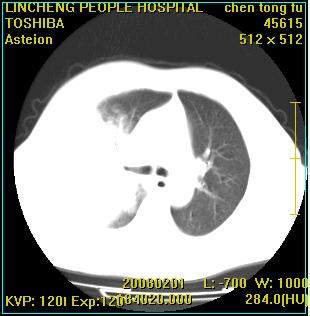

患者,男性,62岁。主因头晕,发热,咳嗽6天,高热达39度,esr19mm/h,wbc 3.9×10 9/l

大叶性肺炎并胸膜炎

右肺大叶性肺炎,胸腔积液。建议痰检。

实变区见空气支气管征,支气管通畅,考虑为大叶性肺炎,右侧少量胸水

右肺大叶性肺炎,胸腔积液,建议严格抗炎治疗后复查.

右肺炎症并右侧胸腔少量积液。

大叶性肺炎并胸膜炎、胸水。

考虑为右肺大叶性肺炎伴少量胸腔积液,建议复查,如病变不吸收或吸收不明显,建议纤维支气管镜检查,除外细支气管肺泡癌的可能。

右侧大叶性肺炎,右侧少量胸腔积液.